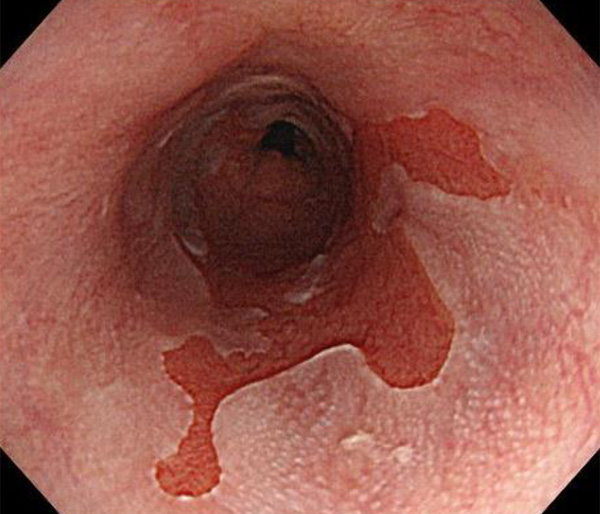

内視鏡所見と病理組織像の1対1対応が可能な症例を公募いたします。主にLSBEに発生した早期癌(HGDを含む)を対象としますが、興味深い症例であればSSBE癌でも結構です。採否は世話人へご一任ください。

症例呈示希望者は応募用紙に記入の上、代表的な内視鏡(2枚)、切除標本(新鮮、固定)、切り出し図、マッピング、代表的組織像とともに、Barrett 食道研究会事務局 barrett.shinshu@gmail.comへお申し込み下さい(10MB以下でお願い致します)。

特に、本邦では極めて稀なlong segment Barrett’s esophagus(LSBE)から発生した早期癌は、診断に難渋する場合も多く、欧米ではランダム生検による検出が標準的とされています。背景のBarrett食道もろとも全体を内視鏡切除+ラジオ波焼灼する欧米と異なり、ESDで内視鏡的な局所切除が基本の本邦では、存在診断+範囲診断(特に水平)を的確に行うことが不可欠です。

そのためには、一流の病理医による組織学的診断とエキスパート内視鏡医による拡大内視鏡像との一対一対応を徹底的に行うことで、『本来、見えないであろう拡大所見の先にある組織構築像が診えてくる』所まで内視鏡診断レベルを上げていく必要があります。その実現には、一対一対応を追究した症例(特にLSBE発生例)1例でも多く経験するしかありません。本研究会でBarrett食道腺癌(LSBE発生早期病変)を共に学び、拡大内視鏡像の一歩先を診るスキルを習得しましょう!一人でも多くの皆様のご参加をお待ちしています。

2026年1月24日開催の第19回研究会でご提示した検討症例です。 (画像をクリックすると拡大します)